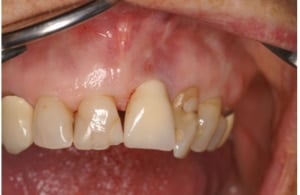

Besloten wordt niet langer af te wachten en operatief in te grijpen en te werken aan een dagelijks toereikende mondhygiëne (gedragsverandering). Het doel is het peri-implantaire weefsel weer gezond te maken en het bot, voor zo ver mogelijk, te regenereren middels het aanbrengen van humane botkorrels en een bindweefseltransplantaat als membraan. Op de foto’s is duidelijk te zien hoe uitgebreid het verval rond het implantaat is.

Situatie vóór en na chirurgie

Situatie 2017 voor chirurgie